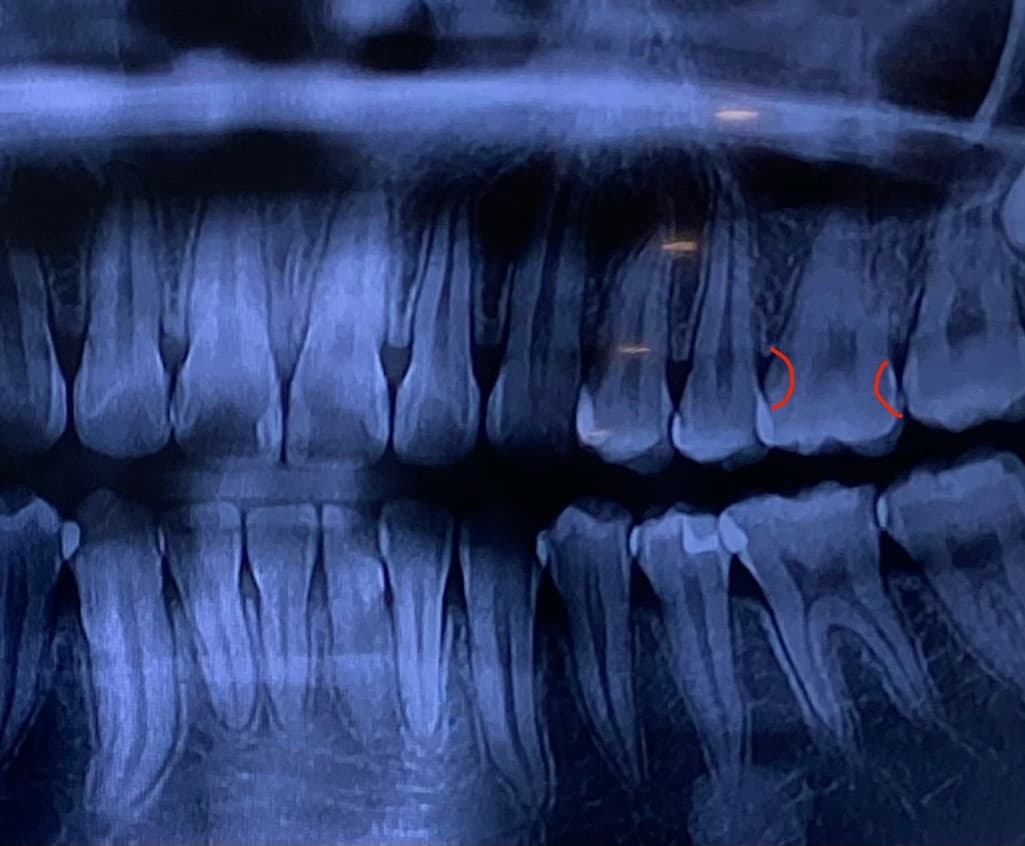

어금니 충치 질문입니다. 좀 봐주셨으면 좋겠습니다.

제가 치아에 충치가 생긴거 같아 치과를 가봤는데 충치가 맞고 육안으로 안 보이는 쪽에도 충치가 있어 인레이 치료를 해야할거 같다고 하셨는데 정말일까요? 일단 원래 가던 치과가 아니라 그냥 검진만 하러 간거라서 검진만 하고 나왔어요. 제가 좀 찾아보니까 레진으로도 가능하다고 하는데 인레이가 더 좋을까요? 레진은 좀 힘들까요? 그리고 인레이로 하면 치아 삭제를 얼마나 해야할까요? 교합면은 멀쩡한데 인레이 치료로 불필요한 삭제는 하는 것은 아닐까요? 질문으로 정리하면

2.인레이를 할 정도로 충치 면적이 넓나요?

엑스레이상 충치가 보입니다